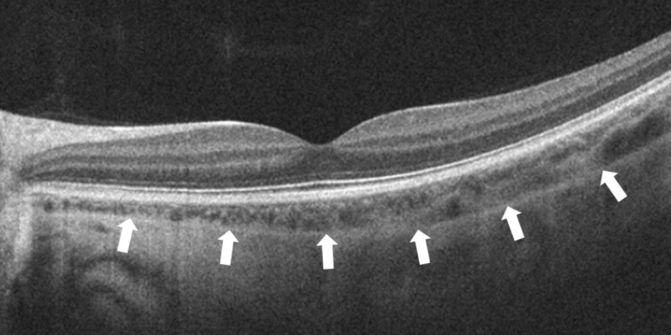

Рисунок «Нормальный профиль фовеа и отграниченная стрелками хориоидея»